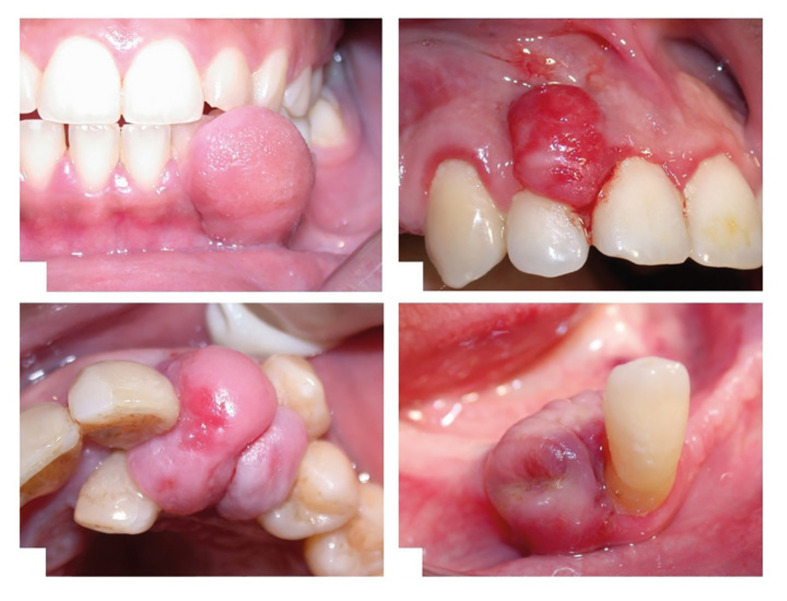

Purpose: Epulis represents a group of reactive hyperplastic lesions occurring in the gingival area, distinct from true hypertrophy, as these lesions involve tissue proliferation rather than enlargement of existing cells. These lesions present significant clinical challenges in diagnosis and management.

Results: Epulis primarily affects young and middle-aged adults with female predilection. The molecular pathogenesis involves complex interactions between local irritants and signalling pathways, particularly aryl hydrocarbon receptor (AhR) and RAS-PI3K-AKT-NF-κB activation. Definitive diagnosis requires histopathological examination, with fibrous, vascular, and giant cell variants exhibiting distinctive features. Surgical excision remains the primary treatment, though emerging evidence supports laser therapy, sclerotherapy, and combination approaches. Preventing recurrence necessitates elimination of local irritants, regular periodontal maintenance, and awareness of patient-specific risk factors.

Conclusions: Clinicians should perform thorough clinical and radiographic examinations to differentiate epulis from malignancies, and consider subtype-specific management strategies, implement comprehensive prevention protocols, and conduct long-term follow-up, especially for high-risk cases. Future research should focus on developing targeted molecular therapies, standardised treatment guidelines, and personalised recurrence prevention strategies.